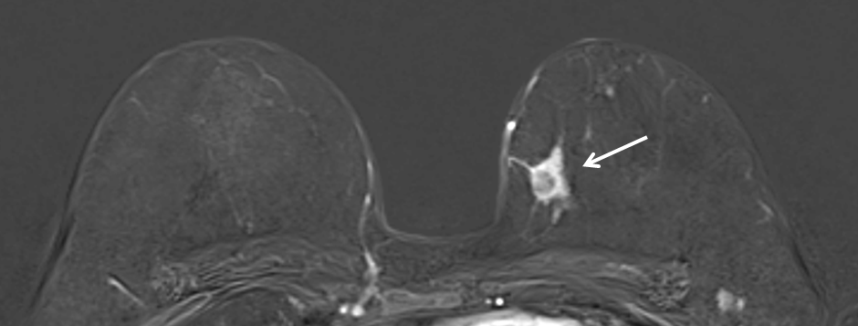

Bei der Kernspintomographie (= Magnetresonanztomographie oder MRT) der Brust werden mit Hilfe eines starken Magnetfeldes Schnittbilder beider Brüste erstellt. Die Untersuchung erfolgt ohne Röntgenstrahlen. Eine Kontrastmittelgabe ist in der Regel erforderlich. Die Kernspintomographie ist eine ergänzende Untersuchung, die bei speziellen Fragestellungen zusätzlich zu Sonographie und Mammographie durchgeführt wird. Bei Patientinnen mit Brustkrebs liefert sie oftmals wertvolle Zusatzinformationen zur Operationsplanung. Weiterhin findet sie bei speziellen Risikogruppen Anwendung, wie zum Beispiel bei Frauen, die bereits einmal wegen Brustkrebs operiert wurden oder Frauen mit nachgewiesen erhöhtem Brustkrebsrisiko, z.B. durch eine bekannte vorliegende Genmutation.

Kernspinuntersuchung einer 55jährigen Patientin mit gesichertem Karzinom in der linken Brust (im Bild rechts, Pfeil)

Die Kernspinuntersuchung der Brust ist nicht generell für die alleinige Brustkrebsfrüherkennung geeignet und kann auch nicht die Mammographie oder die Sonographie ersetzen.